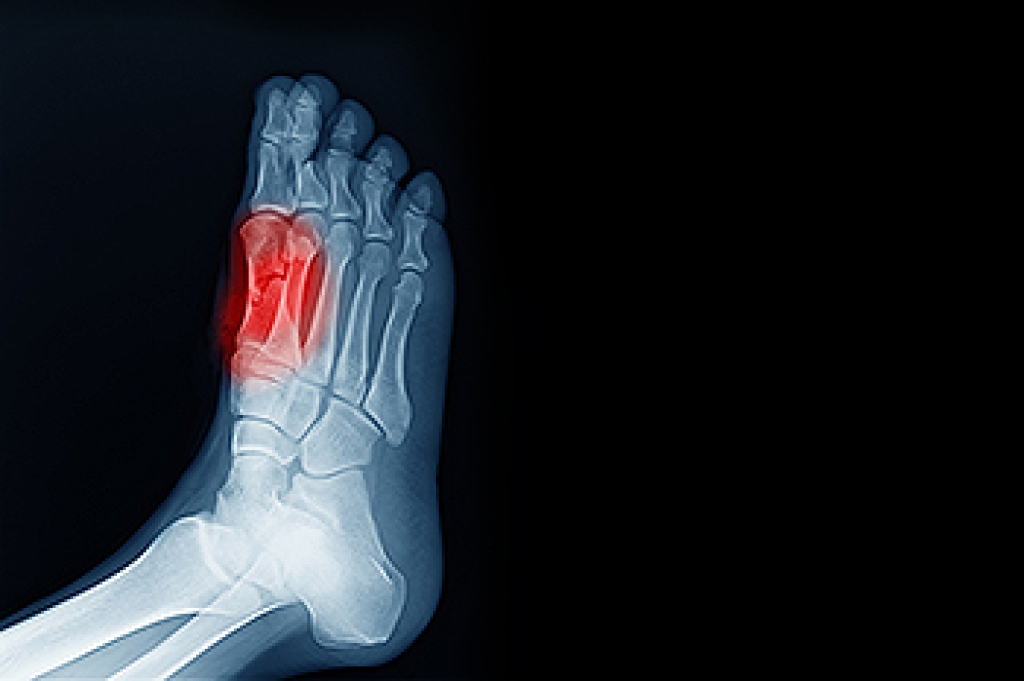

Diabetes poses significant risks to foot health due to its impact on nerves, circulation, and the immune system. Peripheral neuropathy, a common complication, reduces sensation in the feet, making it difficult to detect injuries or pressure points that can lead to foot ulcers. Additionally, impaired blood flow and weakened immunity slow down healing processes, increasing the likelihood of infections that can quickly become serious. Symptoms of diabetic foot problems to watch for include persistent pain, redness, swelling, warmth, and drainage from wounds. These are potential signs of underlying issues that require immediate attention. Regular foot inspections, wearing proper footwear, and regularly scheduled appointments with a podiatrist are essential for preventing diabetic foot problems from progressing. Early intervention not only improves outcomes but also reduces the risk of complications, such as gangrene and amputation. If you have diabetes, learning how to care for your feet and recognizing the early signs of trouble are essential steps in managing your overall health. It is suggested that you add a podiatrist to your team of healthcare professionals for treating diabetes-related foot problems.

Diabetes affects millions of people every year. The condition can damage blood vessels in many parts of the body, especially the feet. Because of this, taking care of your feet is essential if you have diabetes, and having a podiatrist help monitor your foot health is highly recommended.